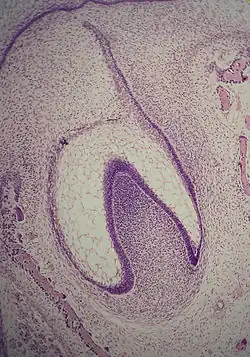

Glockenstadium

Im Glockenstadium findet eine weitere Differenzierung statt. Das Zahnschmelzorgan hat in dieser Phase die Form einer Glocke und die meisten Zellen werden wegen ihrer sternförmigen Erscheinung als „sternförmiges Retikulum“ bezeichnet (Cate 1998:84[1]). Die Zellen an der Peripherie des Zahnschmelzorgans teilen sich in drei wichtige Schichten. Die Zellen an der Außenseite bezeichnet man als äußeres Zahnschmelzepithel.[2] Die Zellen an der Zahnpapille bilden das innere Epithel. Die Zellen zwischen dem inneren Epithel und dem Schmelzretikulum bilden eine Schicht, die man Zwischenschicht (Stratum intermedium) nennt.[5]

Die dentale Lamina zerfällt, wodurch der entstehende Zahn vollständig vom Epithel des Mundes getrennt wird; die beiden verbinden sich erst wieder, wenn der Zahn im Mund hervortritt (Cate 1998:87[1]). Die Krone des Zahns, die von der Form des inneren Epithels beeinflusst wird, nimmt während dieses Stadiums ihre Form an. Alle Zähne durchlaufen diesen Prozess; warum sie unterschiedlich geformte Kronen bilden (z. B. Schneidezähne gegenüber Eckzähnen), ist noch unklar. Zwei Hypothesen dominieren. Eine Theorie besagt, dass es im Ektomesenchym während der Entwicklung Komponenten für jede Form gibt. Die Komponenten für einen bestimmten Typ (z. B. Schneidezähne) werden in einem Gebiet lokalisiert und in anderen Teilen des Mundes schnell abgebaut. Das andere Modell besagt, dass das Epithel eine Gruppe von ektomesenchymalen Zellen programmiert, um Zähne mit einer bestimmten Form zu produzieren. Diese Zellgruppe (Klon) regt die dentale Lamina an, eine Zahnknospe zu bilden. Der Wuchs der Lamina setzt sich in einer „Fortschrittszone“ fort. Sobald sich diese Zone weit genug von der ersten Zahnknospe entfernt hat, entwickelt sich eine zweite Knospe. Die beiden Hypothesen schließen sich nicht unbedingt gegenseitig aus. Die Zahnmedizin geht davon aus, dass beide Modelle die Entwicklung zu bestimmten Zeiten beeinflussen (Cate 1998:89[1]).

In dieser Phase können außerdem Zahnschmelzknoten, -seile und -nischen auftreten (Cate 1998:86[1]).